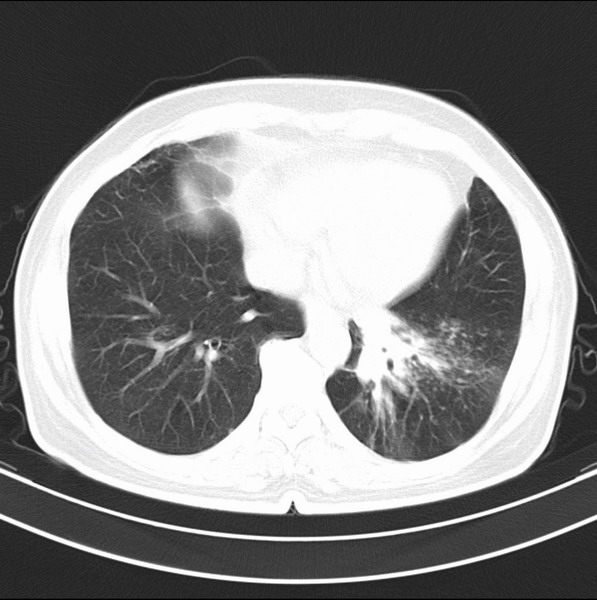

女、63

咳嗽、胸痛四个月

考虑左下肺中央型肺癌

支持左下中央型肺癌伴阻塞性炎症不张。

包绕左下肺基底段的不规则的软组织肿块,段支气管腔变形、狭窄及阻塞性炎症,病变区不规则强化,又是老年女性支持楼上看法。

典型病例:左下肺基底段中央型肺癌,相应支气管狭窄并阻塞性炎症